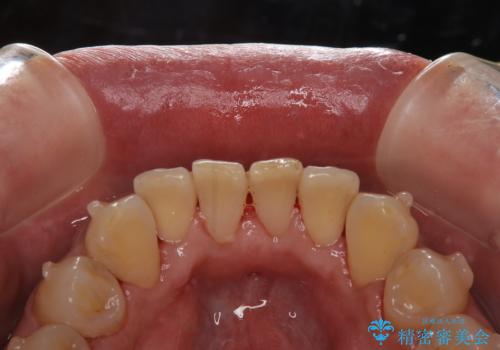

- インビザラインの治療中ですが、歯石やステインが気になるとのことでした。

コーヒーが大好きでよく飲むそうです。

全体的に歯石やステインが付着していたため、エアフロー60分コースを行いました。